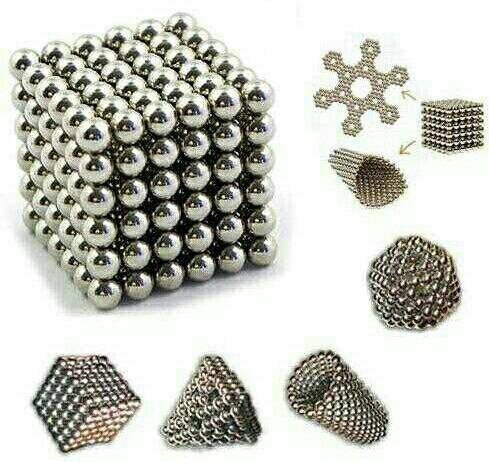

Магнитные шарики на рентгене: Интересные находки